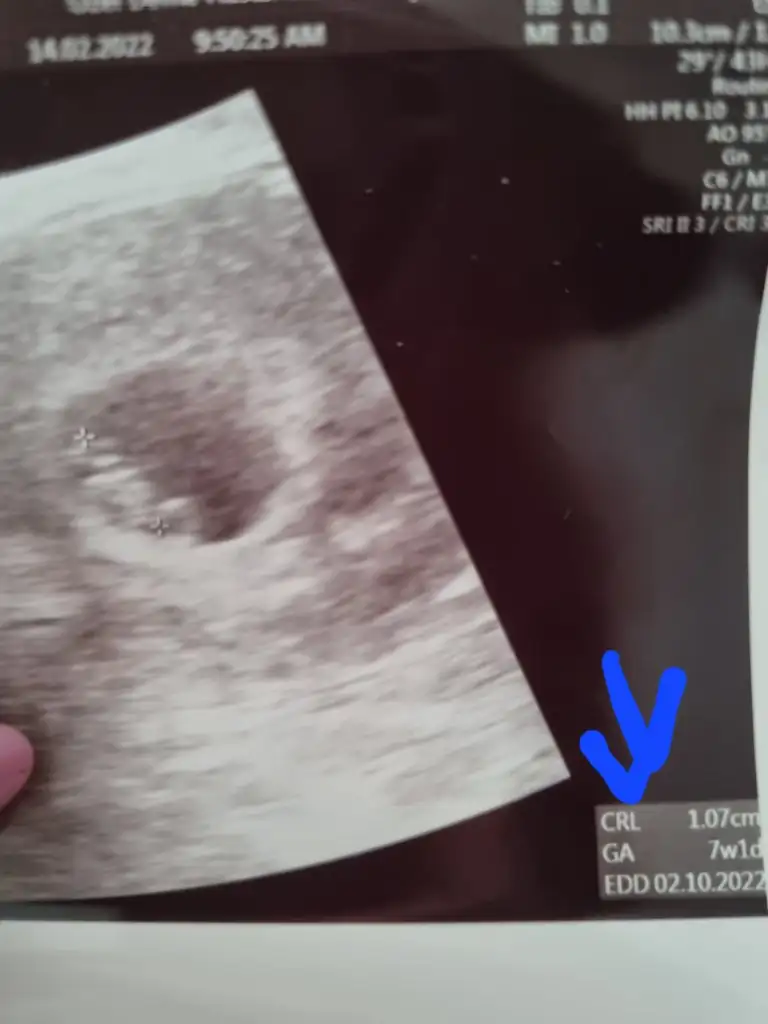

Ama ultrason kağıdının altında da yazıyor, sağ alt köşede hem doğum tarihi, hem haftan hemde bebisin boyu

Baksana kuzu benim sağ altta yazıyor bende internetten baktım anlamlarına, crl bebek boyu, ga haftası, edd tahmini doğum tarihiymis bende ordan biliyorum. Ama seninki ingiliççe pek anlamadımBunlardan başka bir şey yok ki beybisi, hastane ve benim adım dışında.

Bunlardan başka bir şey yok ki beybisi, hastane ve benim adım dışında.Ay minnoş yaakuzum ultrason kagitlarimiz farklı tam halini bi çekip atsana, kıyıda köşede ga veya crl yazan bi yer yok mu